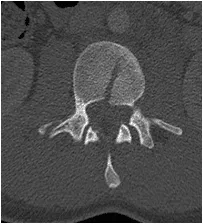

18 yo fell from 3 floors. Near complete loss of all neurological functions below the level of injury with near complete involvement of bowel and bladder

Patient was operated and the spinal canal cleaned up of all bony fragments. The spine was fixed from the side and the back to take care of instability.